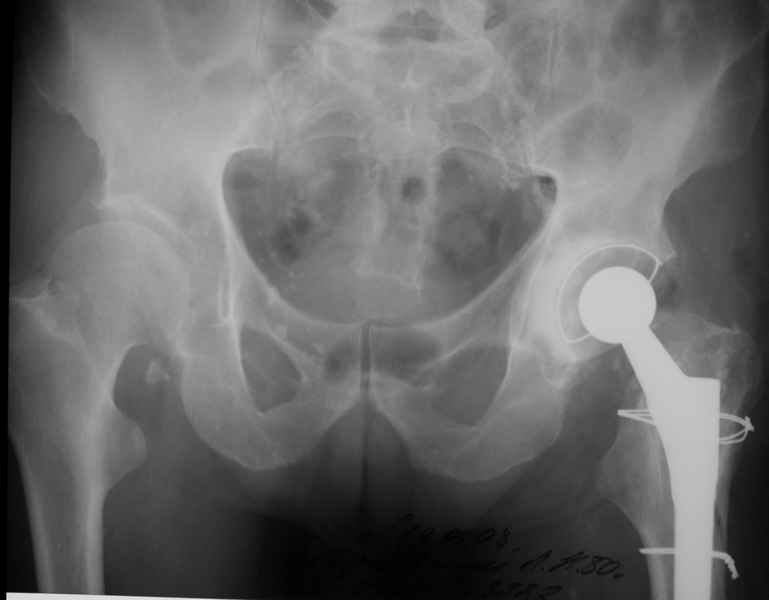

2. Применение ножки дистальной фиксации, мы отдаем предпочтение ножке Вагнера с фиксацией проксимального отдела на ножке. Более травматичное вмешательство, но при стабильной фиксации ножки реабилитация идет в обычном режиме.

Хочется показать два подобных случая, П-ка З. 72 лет и п-т Г. 80 лет. Сразу принимаю замечание, что это были ножки цементной фиксации, просто под руками не было бесцементника.